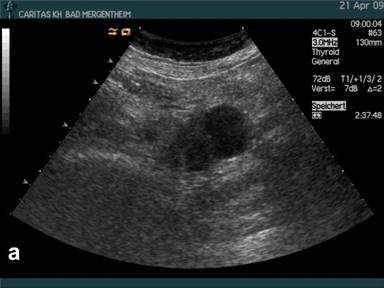

Figure 1. B-mode imaging (a.) and contrast enhanced ultrasound (CEUS) (b.) in a patient with histologically proven pseudocyst of the pancreas. Small peripherally nodular structures are delineated (arrow) analysing the arterial phase (b.) indicating neoplasia. Surgery and consecutive histology revealed pseudocyst and no neoplasia. |

Using conventional B-mode mostly peripherally located solid nodules (with or without septae formation) were displayed in 36/64 (56.3%) patients implying neoplastic disease. The results are shown in Table 2. In 2/36 (5%) of these patients with nodules at the edge of the cyst and the final diagnosis of pseudocyst contrast enhancement was found in the peripherally located solid nodules (Figure 1) which was the reason for the 2 false positive findings using CEUS in histologically/cytologically proven pseudocysts. The pseudocyst transversing arterial macrovessels could only be identified using CEUS and conventional ultrasound in combination in 13/35 (37.1%) patients.